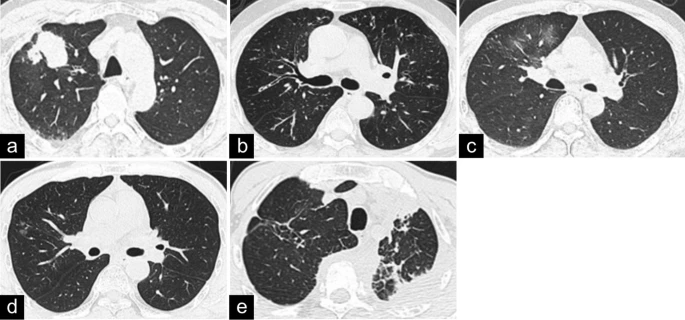

The incidence of pathologically confirmed IgG4-RLD was 0.2% (10/4838). The ten patients had an average age of 59.7 years at diagnosis, and the male-to-female ratio was 9:1. The initial clinical manifestations were nonspecific, and cough was the most common symptom (4/10). More than one organ was involved in most patients (8/10), and mediastinal/hilar lymph node involvement was often observed (7/10). Serum IgG4 was analyzed in 6 patients and found to be elevated. Serum tumor marker levels were within the normal range or were slightly elevated. Computed tomography (CT) of the chest and/or 18F-fluorodeoxyglucose positron emission tomography-computed tomography (18F-FDG PET-CT) imaging revealed that 5 patients had a mixed type, 3 patients had the solid nodular type, and 2 patients had the bronchovascular type. All pulmonary masses and large nodules with solid patterns had spiculated margins and inhomogeneous enhancement with or without pleural indentation and a lobulated appearance. Abundant lymphoplasmacytic cell infiltration and fibrosis were observed in all patients. The expression of IgG4 and IgG was upregulated in the pulmonary sections. Seven patients were treated with glucocorticoids with or without additional immunosuppressants and responded well.